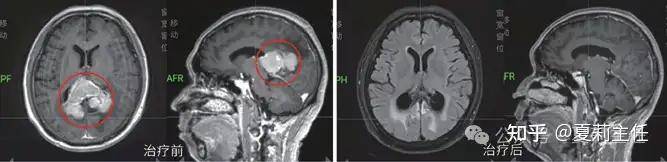

射波刀脑转移临床案例

65岁肺癌患者脑部右侧顶叶有2cm转移灶,经射波刀精准定位治疗,仅3次照射,术后仅轻微头皮发胀。1个月后复查,脑部转移灶明显缩小,患者记忆、肢体功能均正常,日常活动不受限,充分体现其 “精准微创、安全高效” 的核心价值。